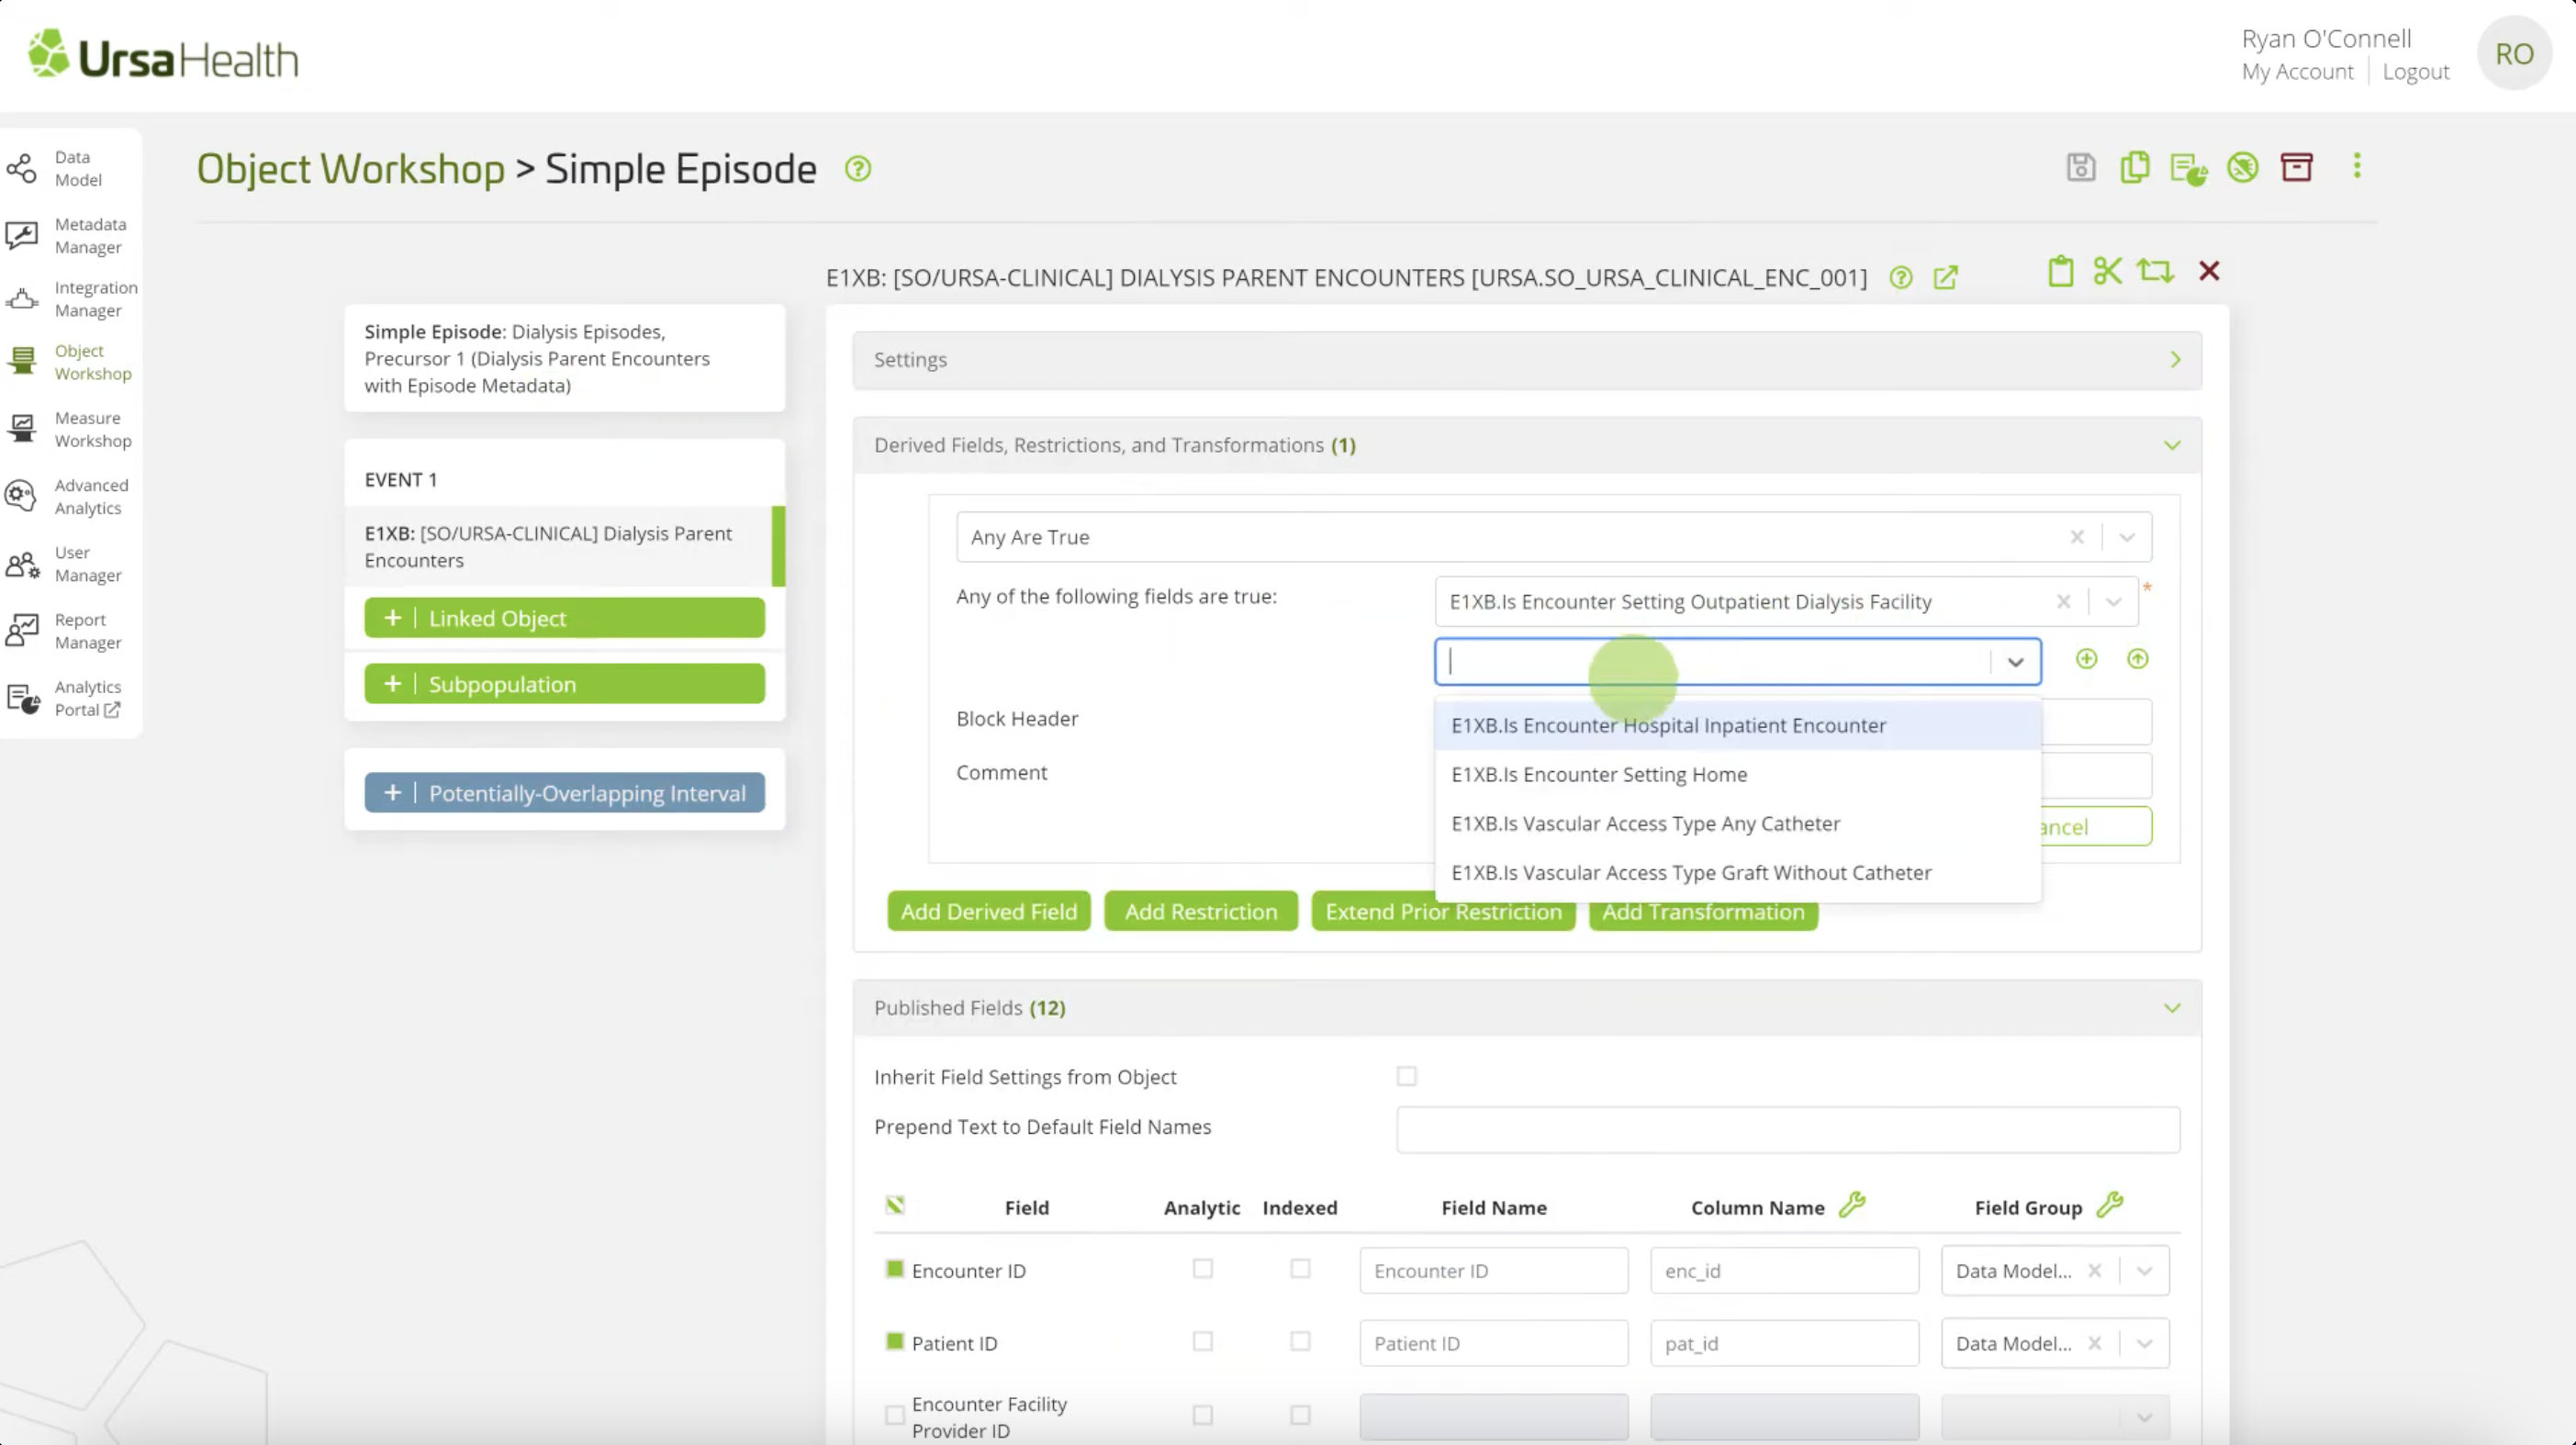

Healthcare organizations creates an analytics development platform that helps you quickly find value in your rich data resources.

Our mission is to create an explainer for Ursa Health database system, an easier access for for the clinical, financial, and operational use.

EXPLAINING VISUALIZATION